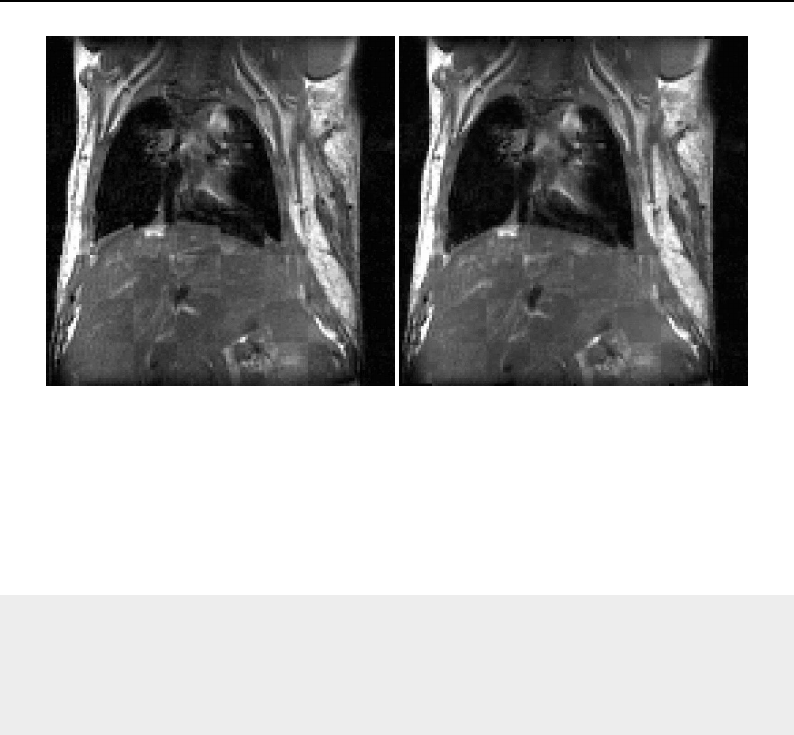

- Deformable Registration

- Demons Deformable Registration

- Visualizing Deformation fields